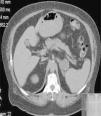

Ante la sospecha de tumor ovárico se realizó una ecografía vaginal sin hallazgos patológicos. Posteriormente se remitió a la paciente a endocrinología, donde se amplió el estudio, solicitándose analítica con marcadores tumorales y pruebas de imagen. En la analítica los niveles de prolactina y el estudio de cortisol fueron normales, así como los marcadores tumorales, a excepción del antígeno carcinoembrionario (CEA), cuyos niveles fueron de 14,5ng/ml (Vn0-5). En la TAC abdominal las imágenes fueron compatibles con adenoma suprarrenal izquierdo (fig. 3). La resonancia magnética de pelvis no mostró imágenes compatibles con tumoración ovárica. Con estos hallazgos se decidió realizar una adrenalectomía izquierda, tras la cual persistieron elevados los niveles de testosterona, con cifras de 4,06ng/ml (Vn0,20-0,80) y el índice de testosterona libre de 42,6 (Vn1,6-6). Finalmente, y dado la alta sospecha de hiperandrogenismo de origen ovárico, se practicó una anexectomía bilateral.